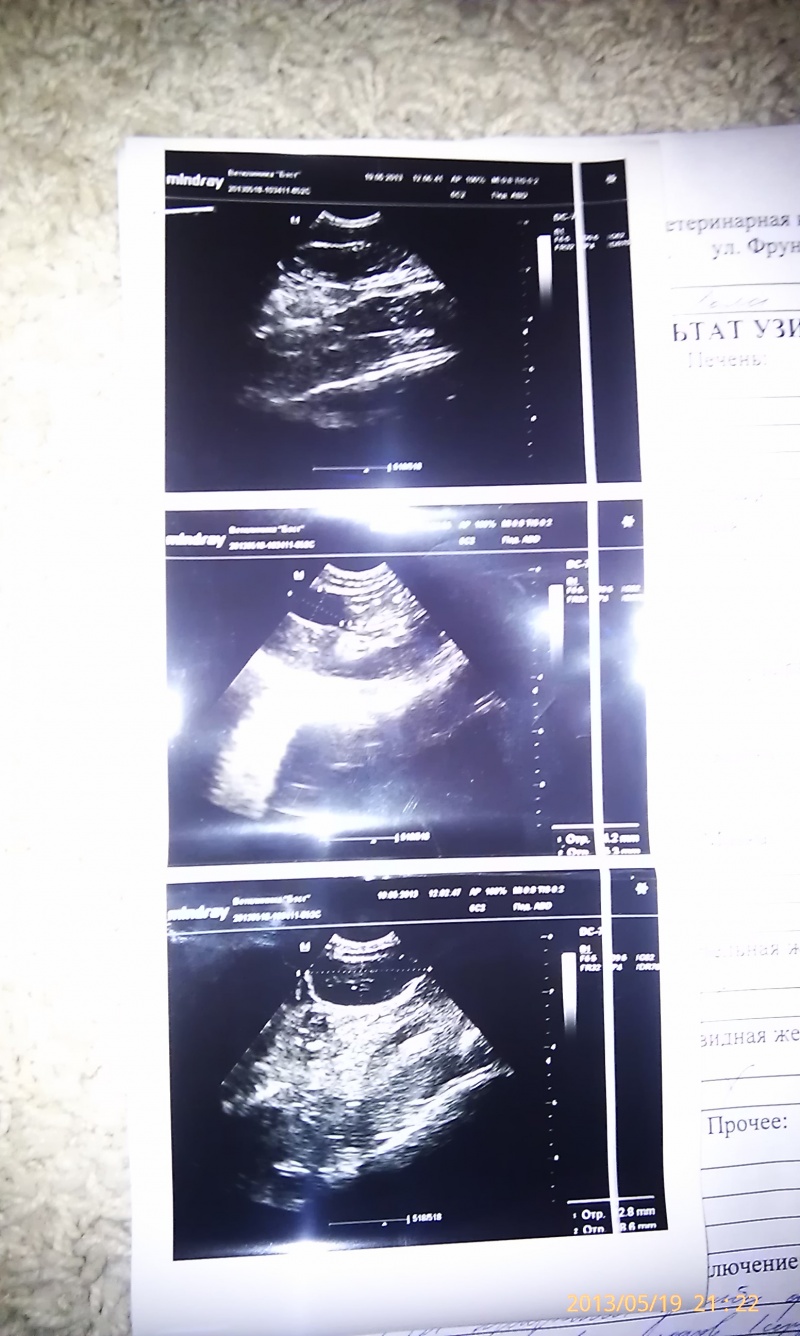

мы приняли решение,забрать у хозяйки Лолу и попробовать её спасти.….19.05 Лолу повезли в клинику ,где есть УЗИ (БЭСТ на Фрунзе). На Узи повреждение внутренних органов не видно из-за плодов (котята умерли),сделали еще раз рентген: ушиб грудной клетки, сломаны лапы!Хирург сказал,что нужно срочно оперировать кошку,пока состояние не ухудшилось! А именно:удаление матки т.к плоды мертвые, осмотр внутренних органов, если что сразу зашивать, и по состоянию кисы установка спиц в лапки! Заранее привезли донора (свою кошку)сдали кровь, Лолу готовят к операции!!!Лечение с такими травмами дорогостоящее, просим о материальной помощи ,рассрочек нет, не потянем единовременную оплату лечения!!Операции будут стоить от 20 т.р и выше,так сказал хирург! Давайте поможем сохранить кошке жизнь!!Дальнейшая информация после операции!!!